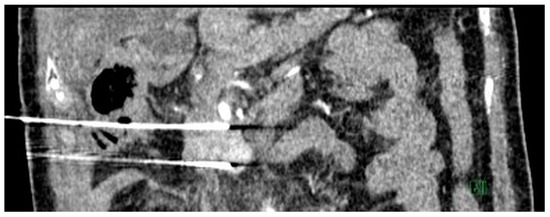

Figure 2.

Intra-operative ultrasound image. Three parallel probe arrays were utilized for open irreversible electroporation (IRE). Open IRE procedural details: Three parallel probe arrays were positioned from medial to lateral, starting from the region besides the superior mesenteric artery. A total of six ablation positions, each with 1 cm tip exposure and five pull backs at each location, was performed. The region besides the duodenal c-loop was avoided to prevent bowel perforation. Ablation using between 80 and 160 pulses at 2000–2500 Volts was delivered at each location (with 12 A rise in current) and monitored under intra-operative ultrasound.